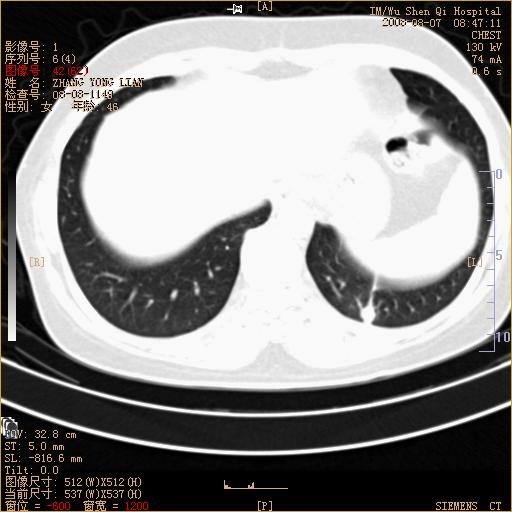

标题: CT15050:女,46岁,咳嗽胸痛一月余 [打印本页]

纵隔窗没发全,左下肺近胸膜处结节。有长毛刺,纵隔淋巴结增大,不排除恶性病变。

考虑肺癌

考虑左肺下叶后基底段周围型肺癌伴纵隔淋巴结转移可能性大。

左下肺ca并纵隔及左肺门区淋巴结转移。

脾脏低密度结节转移不排除。

1)考虑左肺下叶后基底段周围型肺癌伴纵隔淋巴结转移。2)脾内低密度灶,性质待定;不排除转移瘤可能。

考虑左肺下叶后基底段周围型肺癌伴纵隔及肺门淋巴转移。